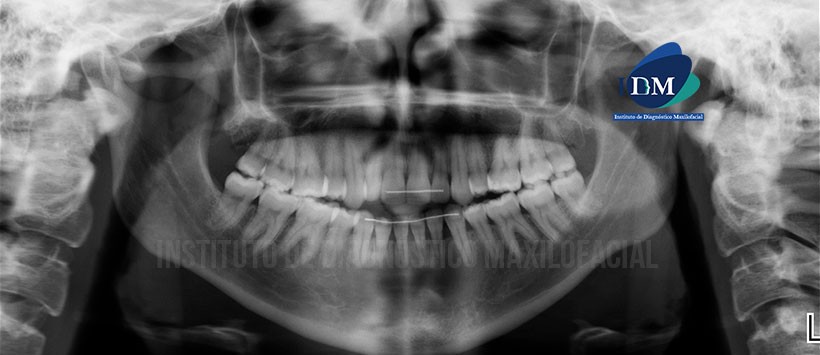

Paciente de sexo femenino de 40 años de edad acude al Instituto de Diagnóstico Maxilofacial para evaluación imagenologica de control.

A la evaluación de la radiografía panorámica se evidencia un aplanamiento del contorno de cóndilo mandibular de lado izquierdo, neumatización alveolar de ambos senos maxilaes, alambre de contención del sector dentario anterior y múltiples restauraciones. (Figura 1)